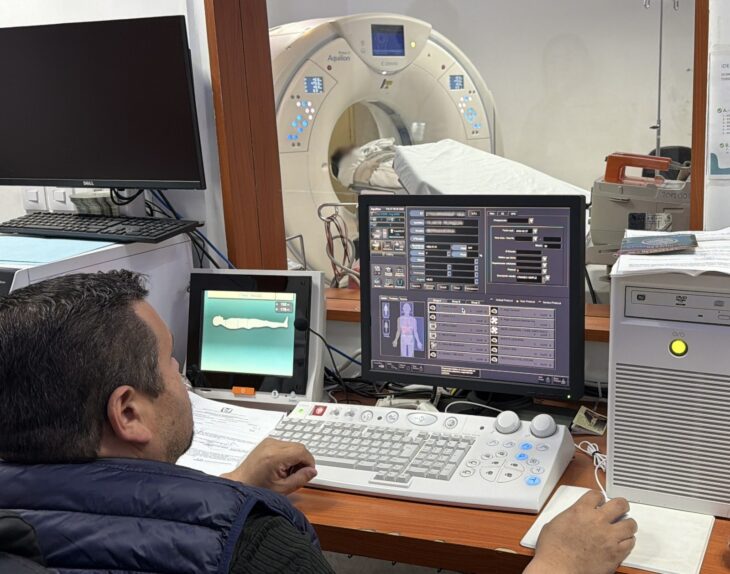

Denuncian desabasto de insumos para quimioterapia en el CECAN

Pacientes que reciben tratamiento oncológico en el Centro Estatal de Cancerología Dr. Miguel Dorantes Mesa (CECAN) manifestaron su inconformidad ante el desabasto de insumos indispensables para la aplicación de quimioterapias, […]